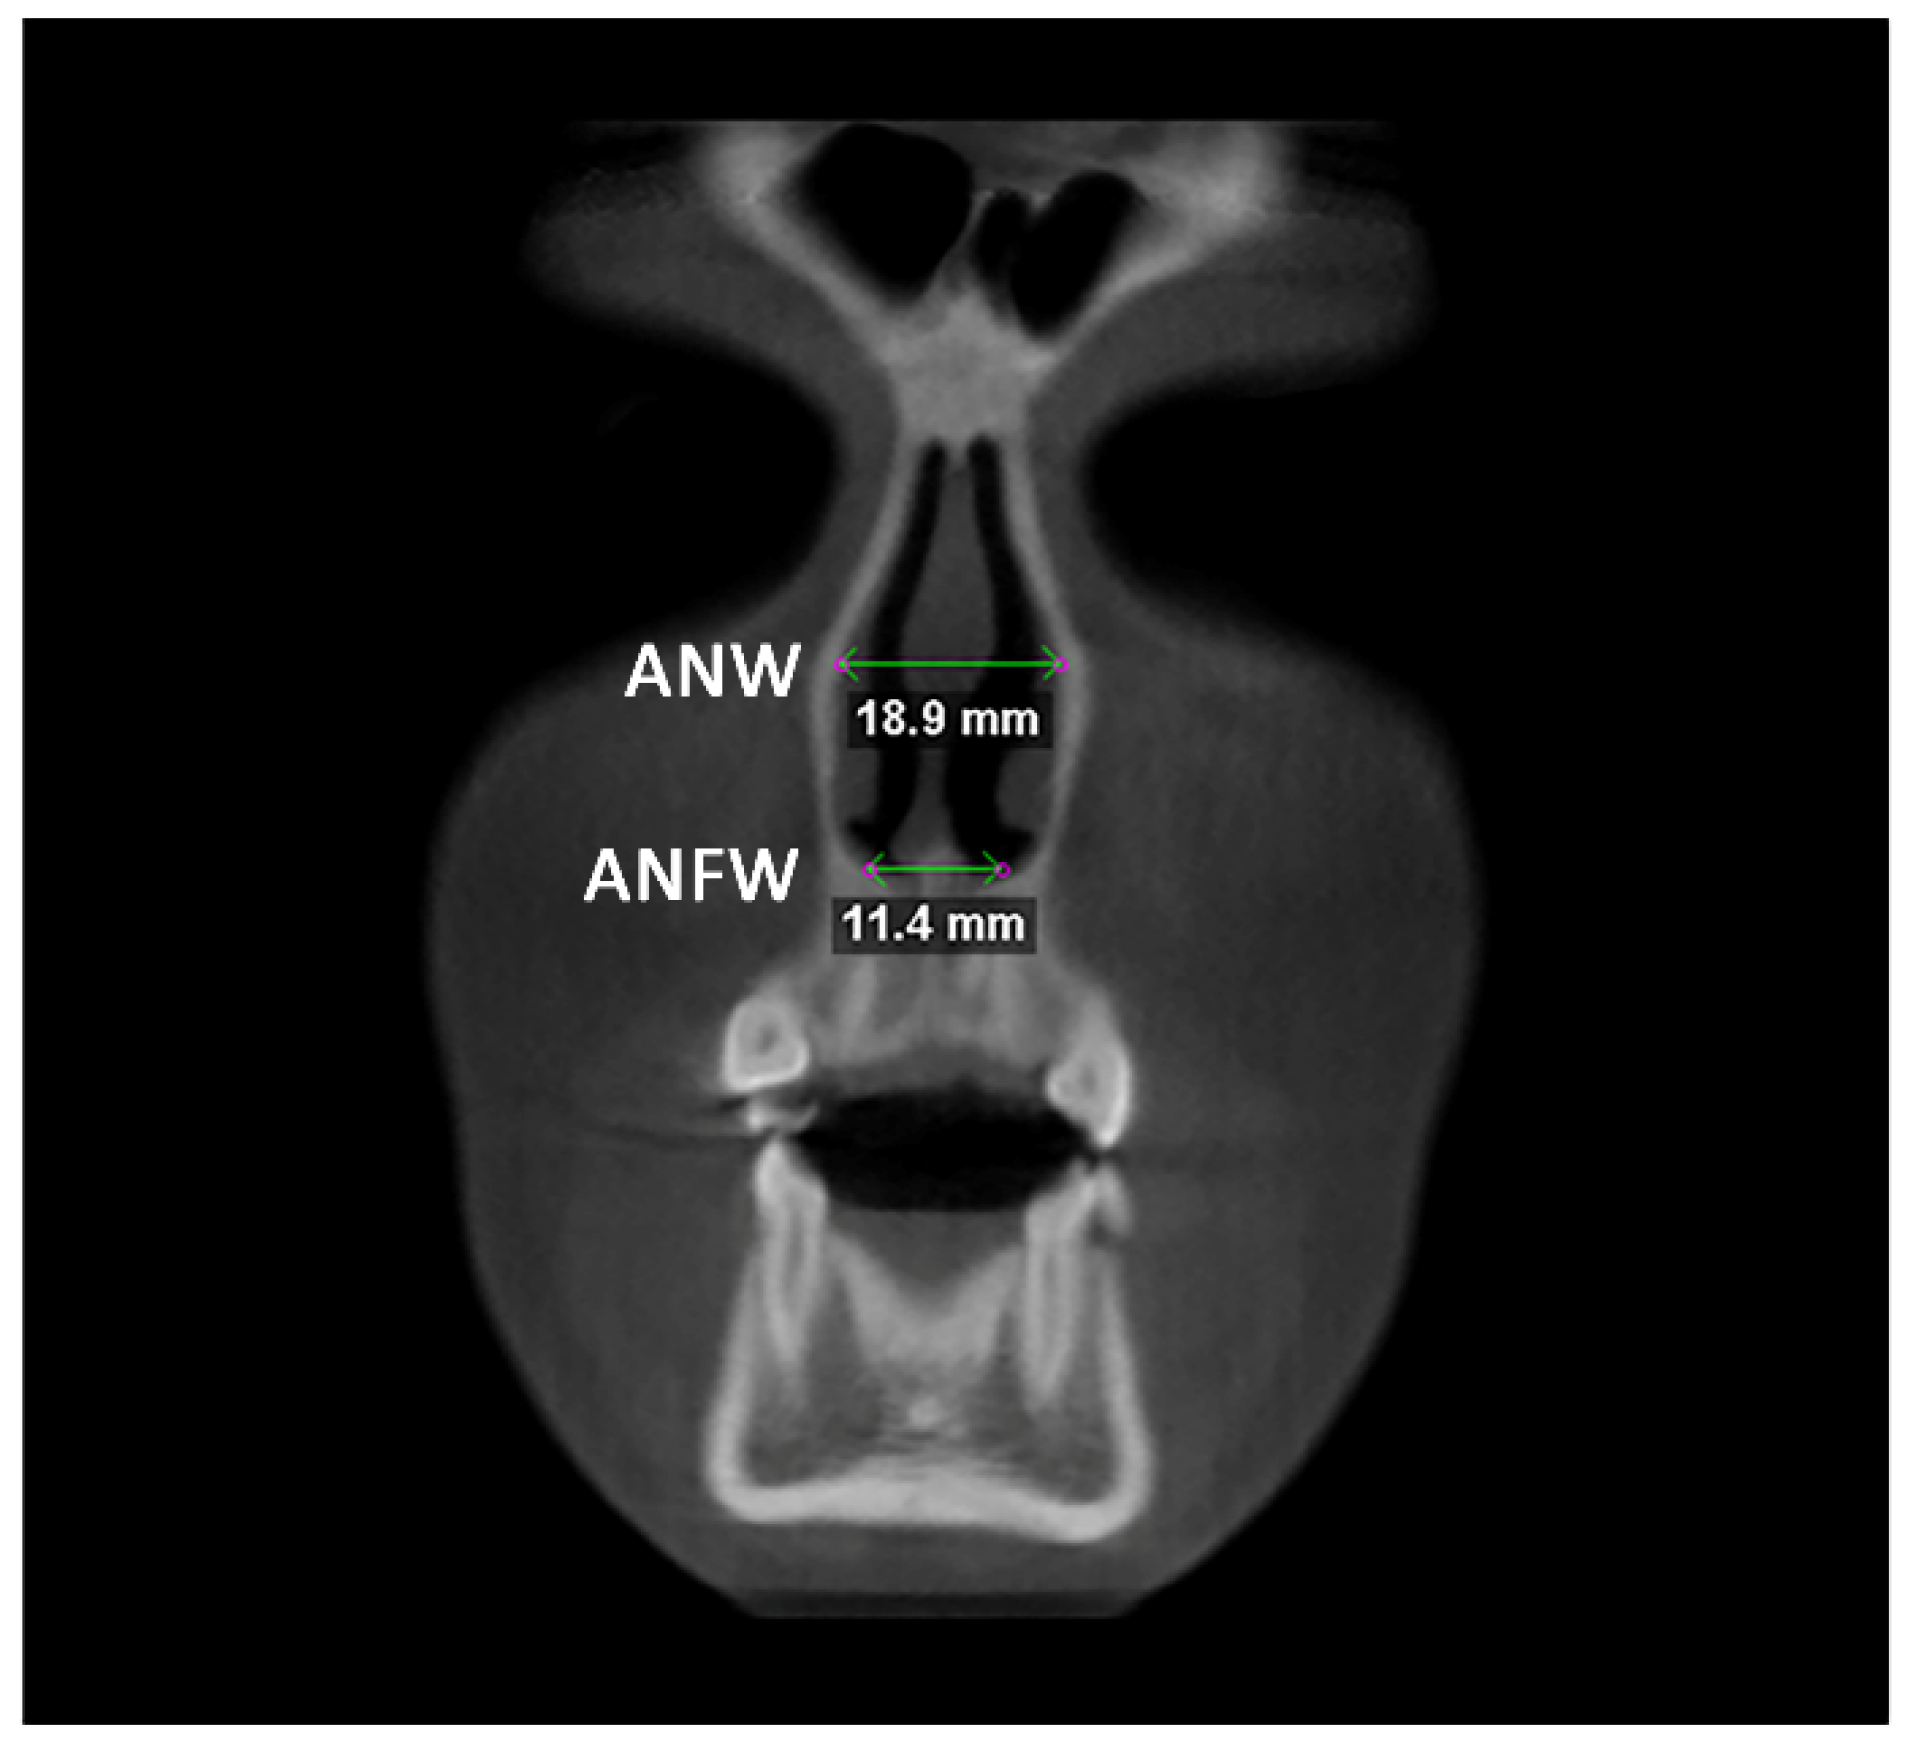

Afterward, the transverse dimension of the Apertura Piriformis was measured in the anterior and posterior regions. In the coronal plane passing through the cephalometric point N, the linear measurements of anterior nasal width (ANW) and anterior nasal floor width (ANFW) were performed (Figure 3, Table 1). Similarly, in the coronal plane passing through the upper margin of the mesial aspect of the Sella Turcica, the linear measurements of the posterior nasal width (PNW) and posterior nasal floor width (PNFW) were performed (Figure 4, Table 1). The entire procedure for skeletal measurements was performed by using the Dolphin 3D software (Dolphin Imaging, version 11.0, Chatsworth, CA, USA).

Figure 3.

Linear measurements of anterior nasal width (ANW) and anterior nasal floor width (ANFW) in the coronal plane.